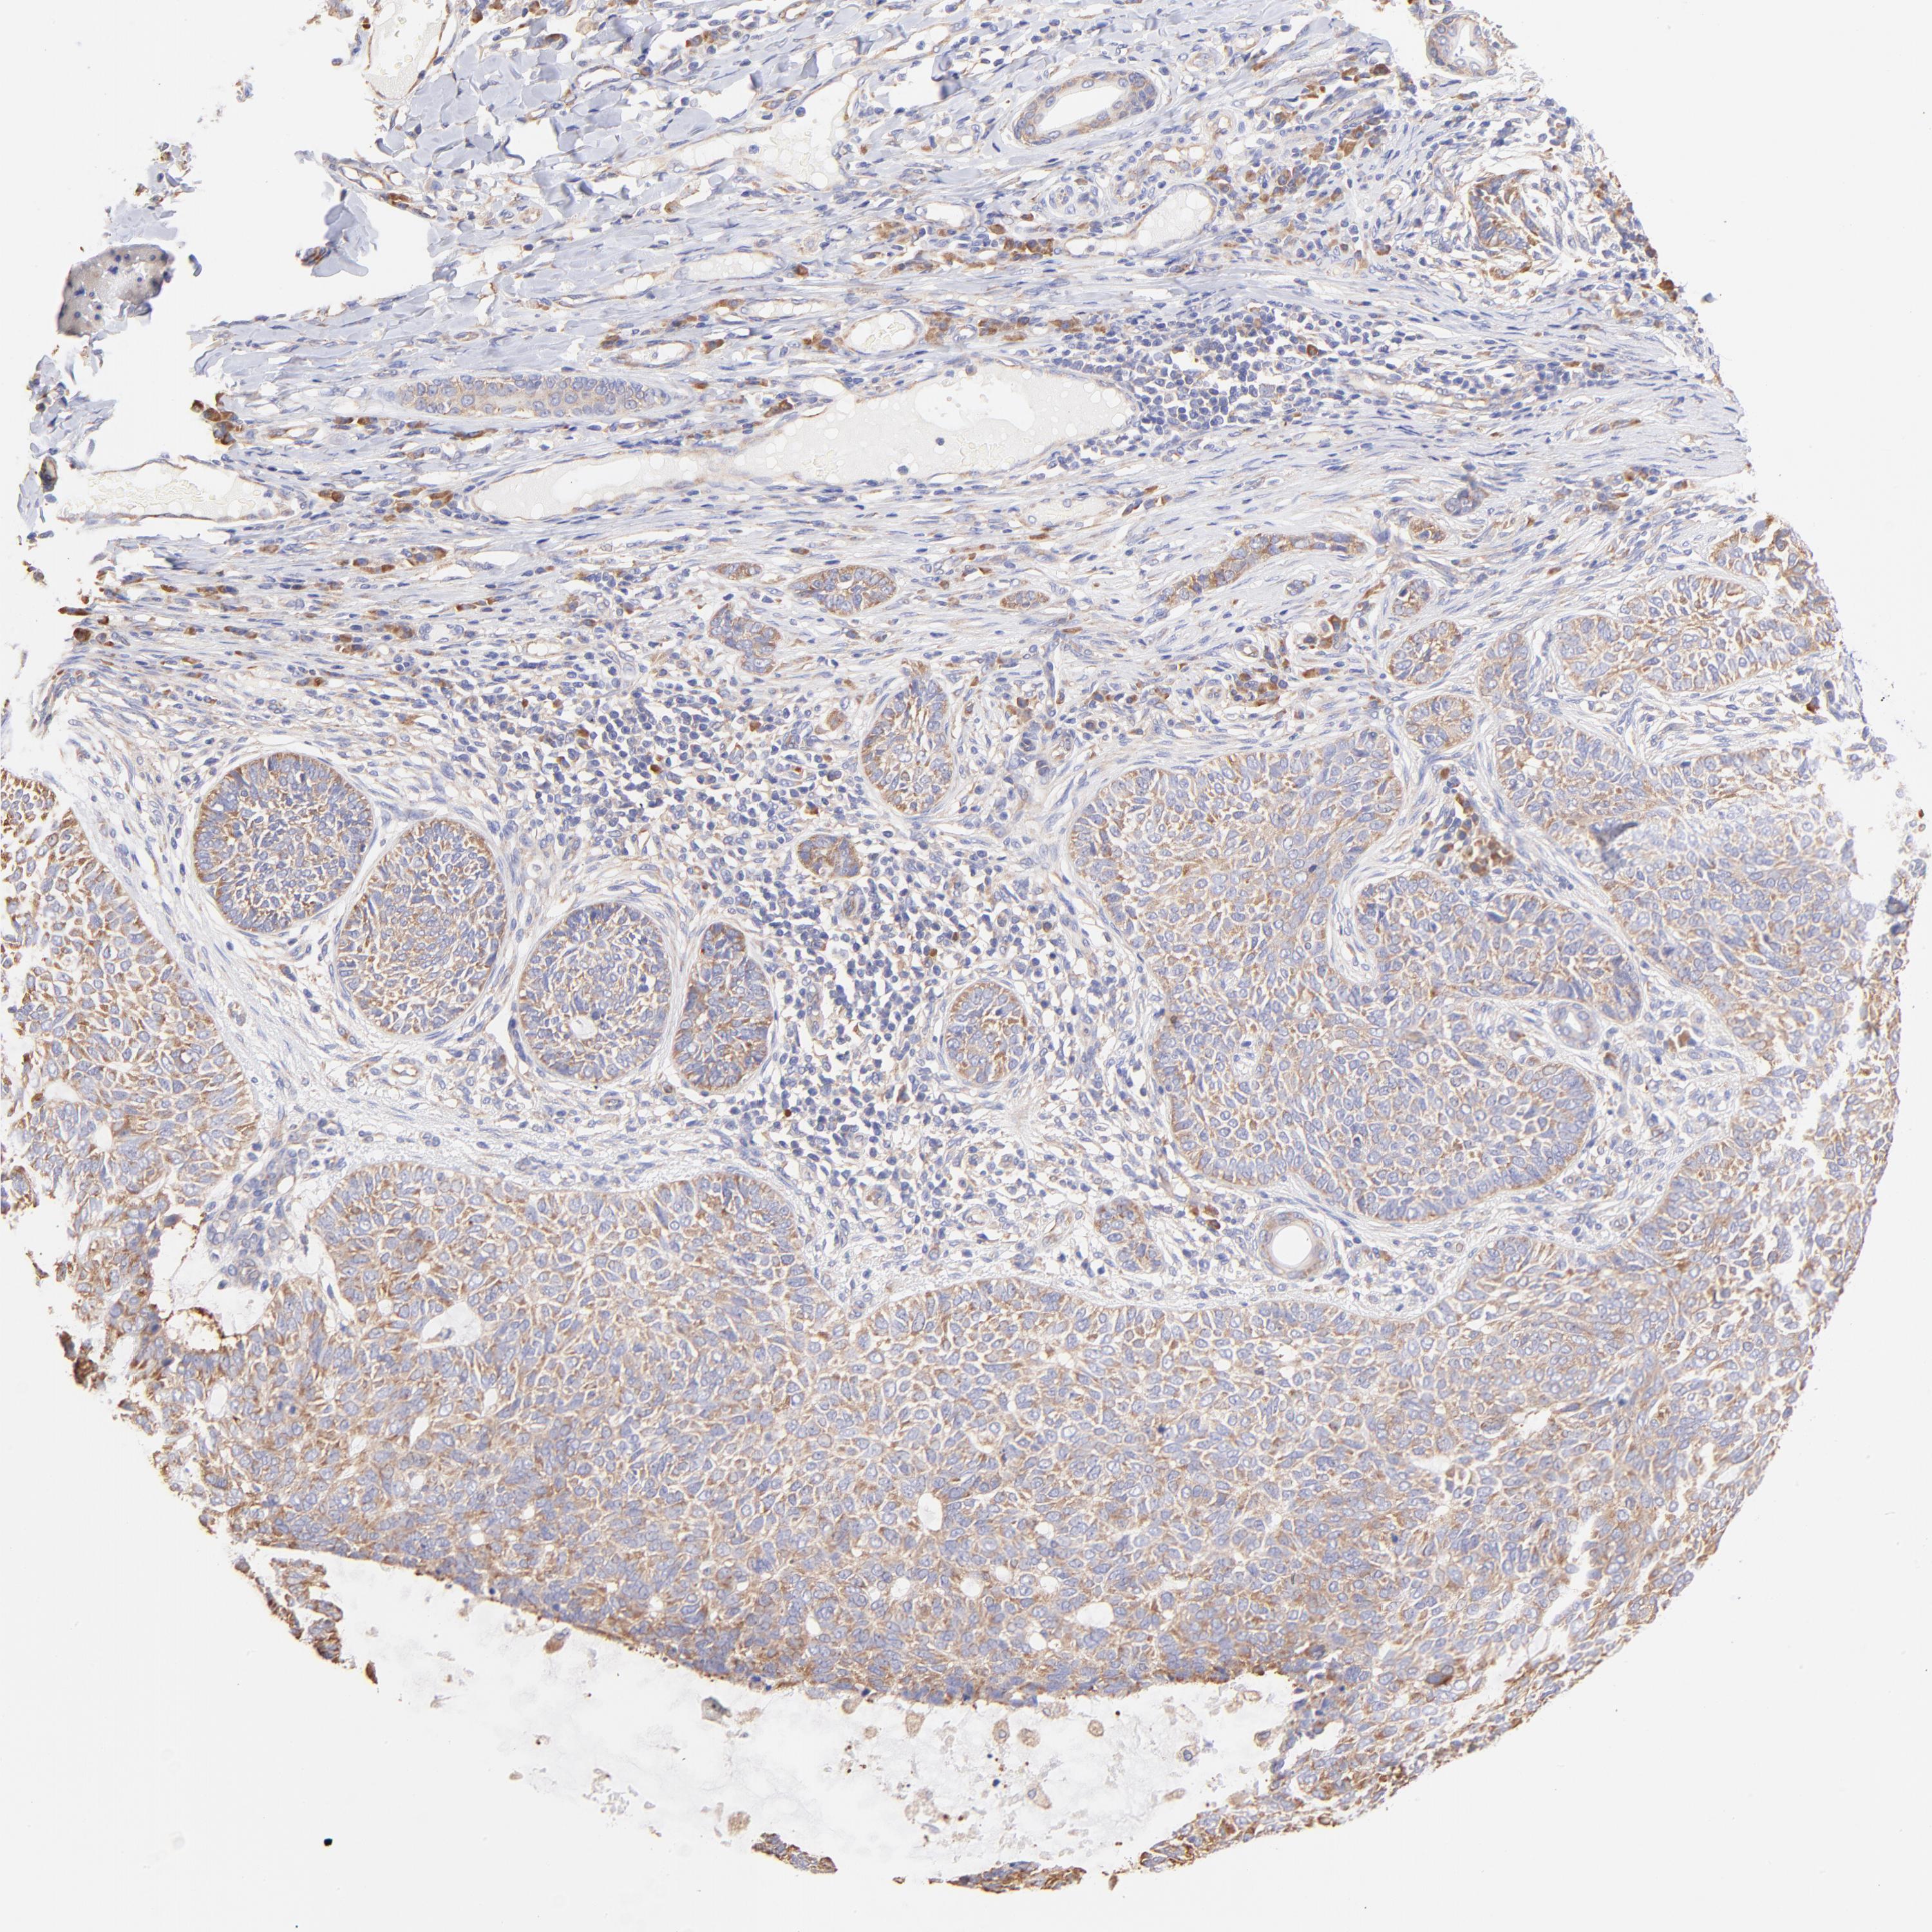

SKIN CANCER - Protein expressioni

A mouse-over function shows sample information and annotation data. Click on an image to view it in a full screen mode. Samples can be filtered based on level of antibody staining by selecting one or several of the following categories: high, medium, low and not detected. The assay and annotation is described here.

Antibody stainingi

Antibody staining in the annotated cell types in the current human tissue is reported as not detected, low, medium, or high, based on conventional immunohistochemistry profiling in selected tissues. This score is based on the combination of the staining intensity and fraction of stained cells.

Each image is clickable and will lead to virtual microscopy that enables deeper exploration of all samples and also displays staining intensity scores, fraction scores and subcellular localization as well as patient and tissue information for each sample.

Antibody HPA002651

Staining

High

Medium

Low

Not detected

Intensity

Strong

Moderate

Weak

Negative

Quantity

>75%

75%-25%

<25%

None

Location

Nuclear

Cytoplasmic/membranous

Cytoplasmic/membranous,nuclear

Squamous cell carcinoma, NOS

Basal cell carcinoma